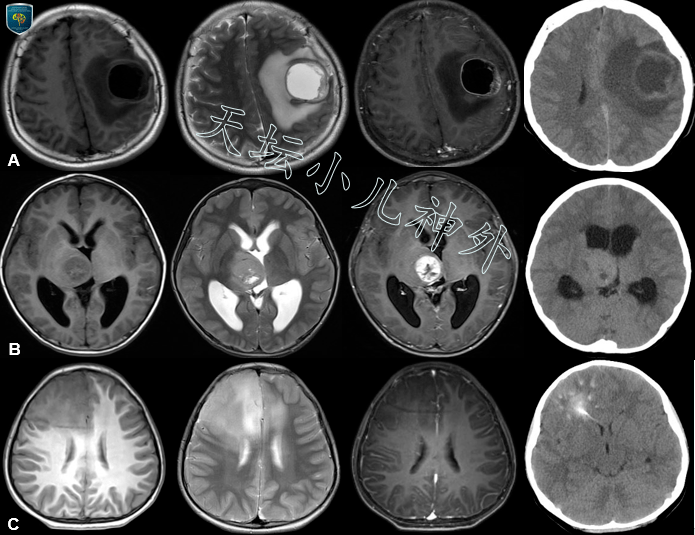

天坛小儿神外宫剑教授访谈儿童型弥漫性高级别胶质瘤的解读与天坛诊疗

图片尺寸695x535